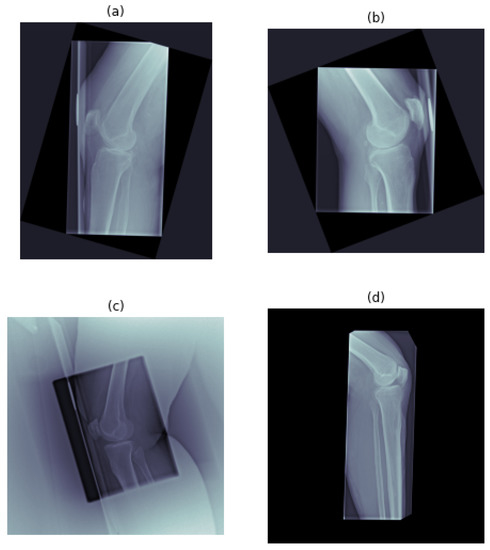

The dataset was collected at the University Hospital of South West Jutland in Esbjerg, Denmark, through the standard diagnostic procedure, using a Ysio Max Digital Radiography system (Siemens Healthineers, Erlangen, Germany). Patients were positioned standing (weight-bearing), with the lateral side of the knee towards the image detector. The dataset consists of 4000 lateral knee XE, of which half are right knee (RK) XE and half are left knee (LK) XE. The data labeling of the XE as “acceptable” and “unacceptable” was performed by two reporting radiographers and used as the reference standard. Within each of the RK and LK datasets, half of the XE were labeled as “acceptable” and half as “unacceptable”, for 2000 XE of each class in total. An example of the XE in the dataset is given in Figure 2.

Figure 2. Example of used XE, per each class: (a) right-oriented, acceptable; (b) left-oriented, acceptable; (c) right-oriented, unacceptable; and (d) left-oriented, unacceptable.